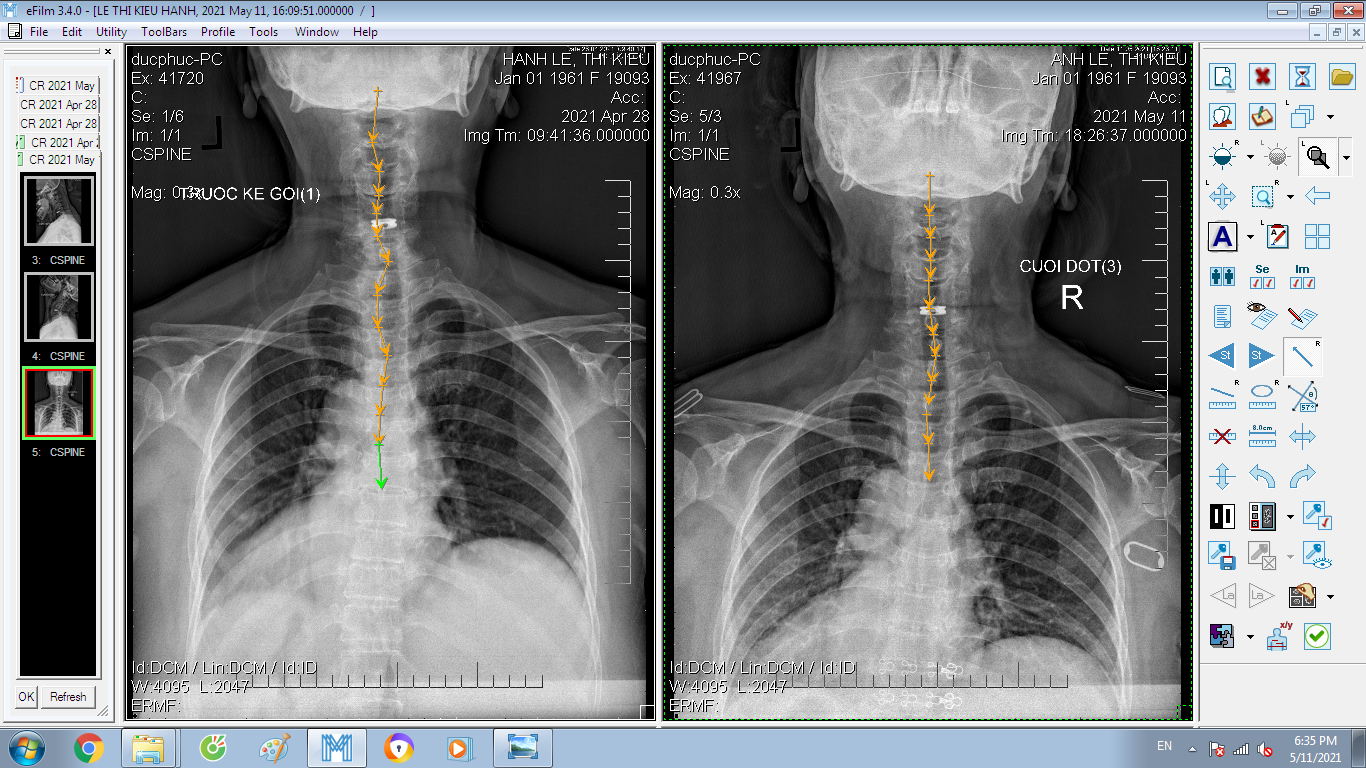

DOCTORLOAN đã thành công trong điều chỉnh xương khớp về đúng vị trí trong thời gian ngắn